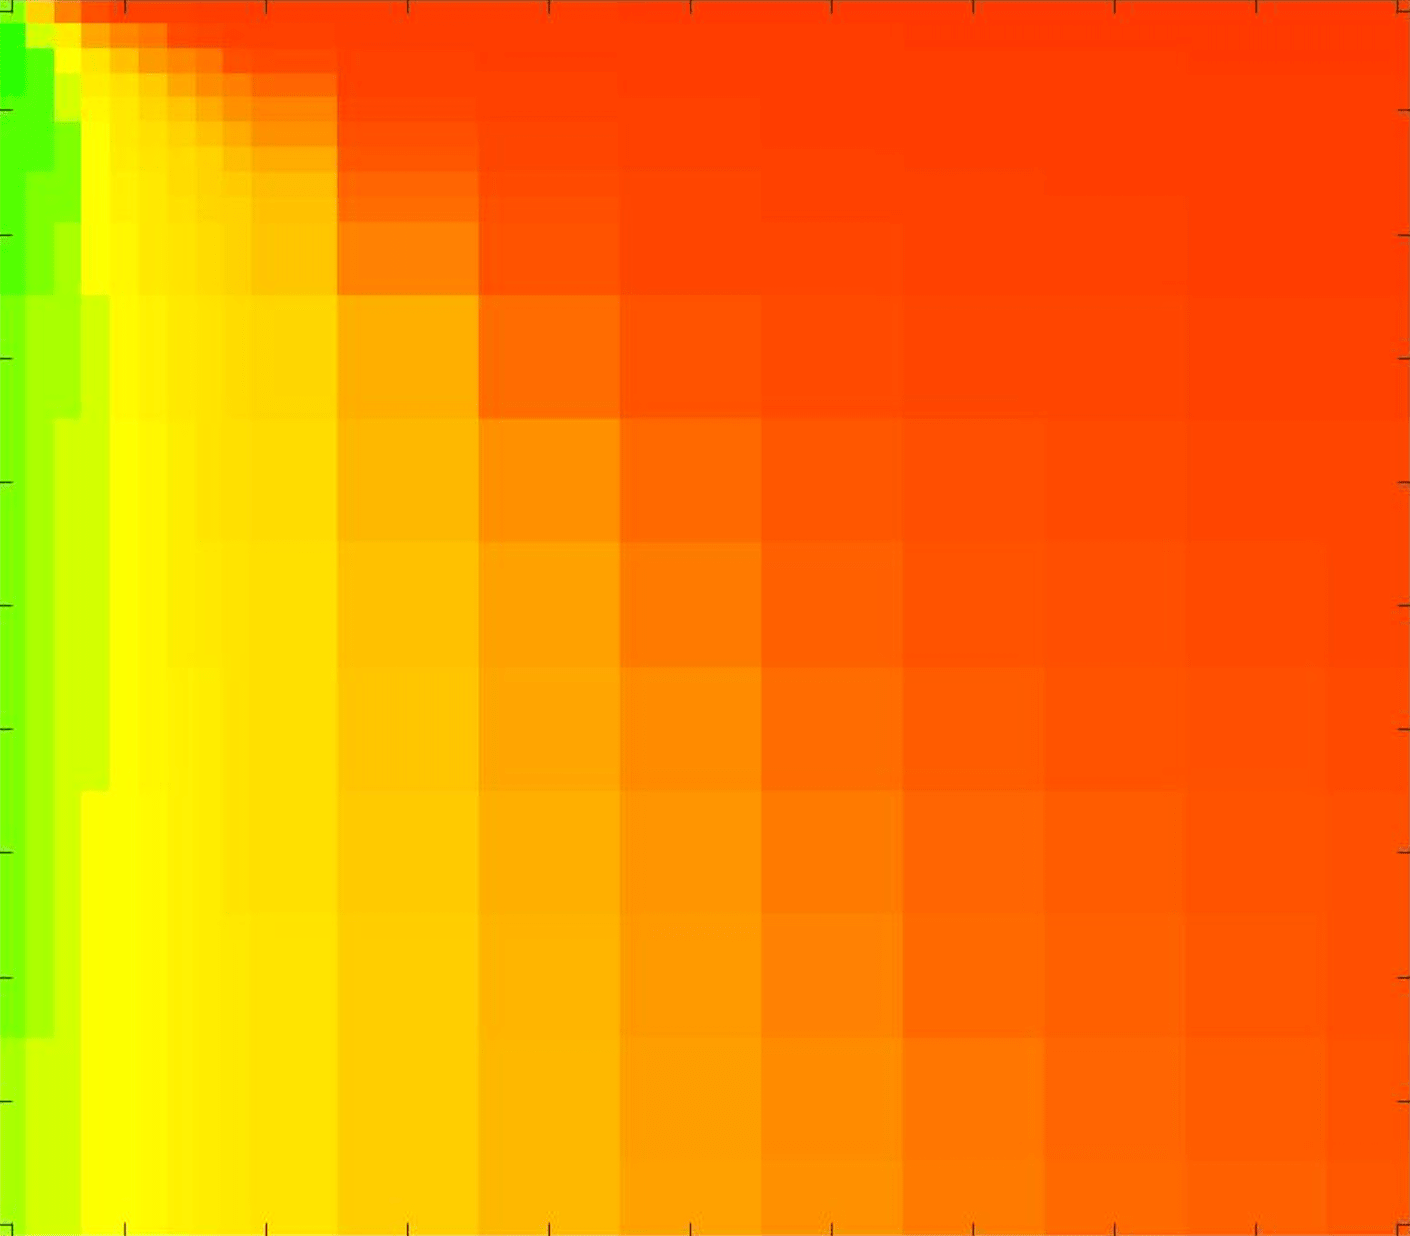

In these tests we aim to demonstrate how sensitive to parameter choices each choice of fitting term is. To accomplish this we perform the segmentations for each of the models discussed (CV, RSF, LCV, HYB, GAV) and the proposed model for a wide range of parameters and compute the TC value. The parameter range used is . Due to computational constraints, we run for each integer between 1 and 10, and every fifth from 15 to 50. This aspect of a model’s performance is vital when used in practice. The less sensitive to parameter choices a model is the more relevant it is in relation to potential applications. It should be noted that we neglect to test the selective models detailed in §3 with respect to parameter robustness as we are using the authors’ implementation of each approach. Instead, we make direct comparisons in the following sections.

The TC values for the parameter sets are presented as heatmaps in Figs. 11–13. A heatmap is a convenient way to display accuracy results for hundreds of tests concisely. In Fig. 9 we give an example heatmap with the same axes used for those in Figs. 11–13. For each of the combinations of parameter values we give the TC value of the segmentation result and represent it by the appropriate colour. The corresponding colour scale is shown in Fig. 8. Qualitatively, the more green areas of the heatmap the more accurate the model is for a wider set of parameters. Example results for Test Image 5 when varying (with ) for the proposed model are given in Fig. 10. Here it can be seen what each accuracy result corresponds to visually.

Synthetic Images. These results are presented in Fig. 11. For Test Images 1–2 we see poor parameter robustness from all competing models, except for GAV which performs reasonably well. However, the proposed model has minimal parameter sensitivity for these images, with good results achieved for almost every combination of values tested. For Test Image 3 all models have a reasonable parameter range (except for RSF), however the proposed model gives better quality results for a wider parameter range. The other models achieve reasonable results here as the foreground intensity of the ground truth is greater than the background , whereas for Test Images 1–2 they are equal . These results highlight the key advantage of the proposed model.

Real Images. In Fig 12 we present results for Test Images 4–6. Here, the proposed model performs in a similar way to its competitors because these images are more typical selective segmentation problems in the sense that there is a clear distinction between the foreground and background intensities. In particular, the values in each case are: Test Image 4 , Test Image 5 , and Test Image 6 . It can be seen that the proposed model is competitive compared to previous approaches. The performance is quite poor for Test Image 5, but is arguably still the best for this challenging case. In Fig. 13 we present results for Test Images 7–9. Here the proposed model outperforms previous approaches significantly for each image. This is mainly due to the type of image considered. Specifically, the true intensities are: Test Image 7 , Test Image 8 , and Test Image 9 . The proposed model is capable of achieving results where , with other models failing completely in these cases.